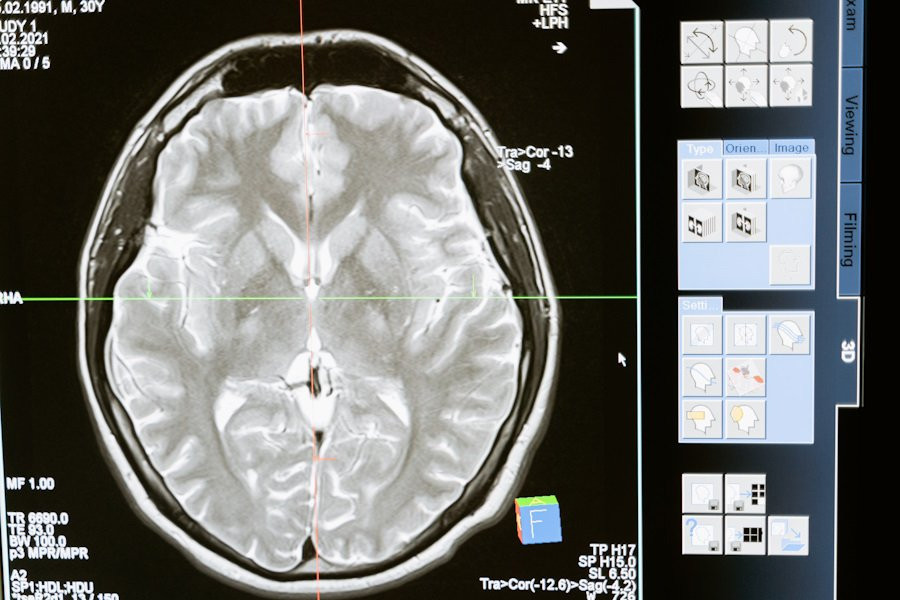

Их работа сфокусировалась на использовании двух- и трехмерных моделей компьютерного зрения, основанных на анализе данных магнитно-резонансной томографии (МРТ) мозга, как с использованием контрастного вещества, так и без него.

Новый модуль способен выявлять и классифицировать четыре основных типа опухолей головного мозга: менингиому, невриному, глиобластому и астроцитому. Это позволяет специалистам точно определить характеристики опухолей, такие как их компоненты и размеры, что является важным шагом в борьбе с этими опасными заболеваниями.